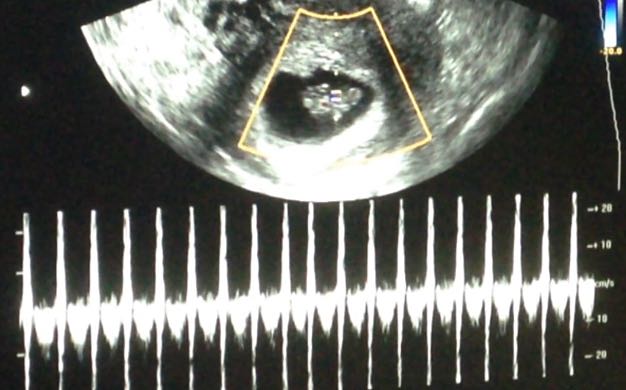

Una vez allí, me exploraron (os recuerdo que estoy con progesterona, ya que ayuda a mantener "tranquilito" al útero, y así evitar contracciones que me puedan acortar el cuello del útero), así que me exploraron, como yo digo, por arriba y por abajo, el cuello del útero estaba perfecto, y cuando me pusieron a la peque en pantalla, en la eco abdominal, y vi el movimiento del corazón y los colorcitos azul y rojo... ¡¡AYY QUE TRANQUILIDAD!! El doctor me puso el latido de Claudia, y escucharlo fue una maravilla, que sonido tan bonito y perfecto. Me evaluaron que la bolsa no tuviera ninguna fisurita, que la placenta estuviese bien, que Claudia estuviese perfecta... y me dijeron que todo estaba perfectísimo.